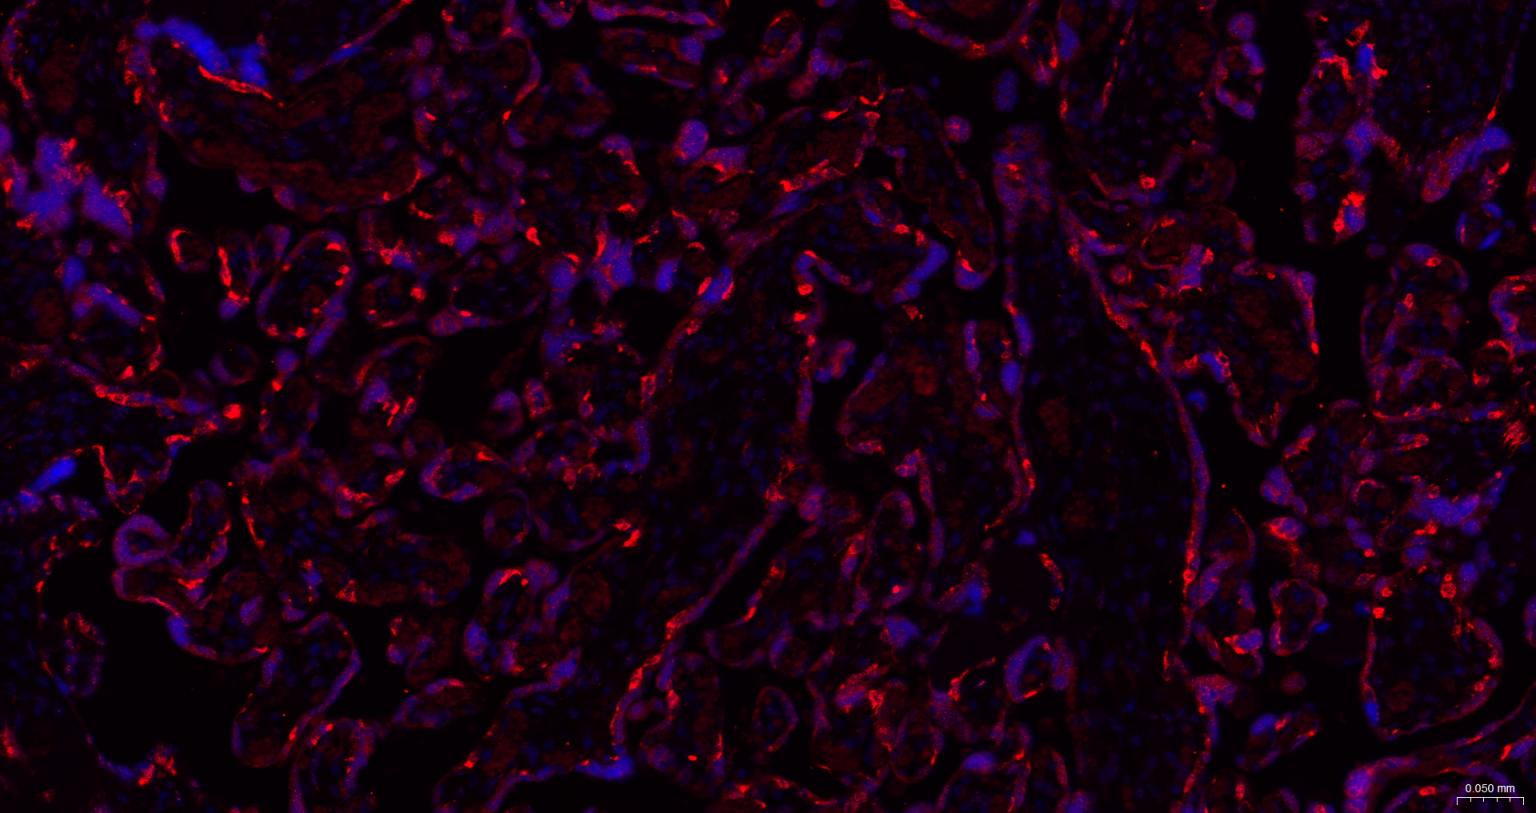

Paraformaldehyde-fixed, paraffin embedded Human Placenta; Antigen retrieval by boiling in sodium citrate buffer (pH6.0) for 15 min; The section was incubated with MSI2 Monoclonal Antibody, Unconjugated (bsm-61244R) at 1:200 overnight at 4°C. Followed by conjugated Goat Anti-Rabbit IgG antibody (Red, bs-0295G-BF594), DAPI (blue, C02-04002) was used to stain the cell nuclei.